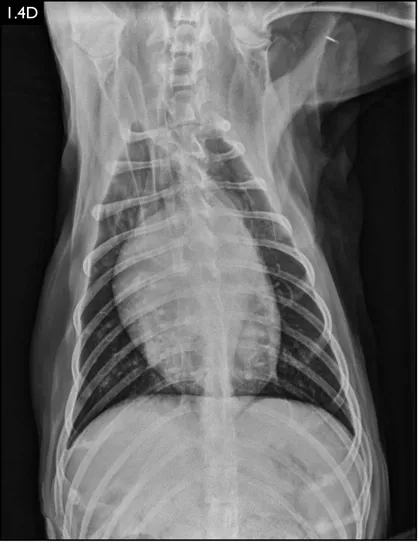

Clinical signs can be strongly suggestive of bacterial pneumonia, but radiographs are important for confirmation, to characterize the disease (and potential etiology) and to provide a baseline for monitoring response to treatment (Figs. 1.4–1.6). A lag between clinical signs and radiographic changes can occur, and initial radiographs may be normal or appear discordant with clinical severity.

Fig. 1.4A–D Lateral and ventrodorsal radiographs of a dog with doxycycline-responsive pneumonia of unknown etiology before treatment ( A, B) and six days later ( C, D). Note the severe multilobar alveolar pattern that was present initially, most prominently in the left cranial lung lobe. (Courtesy of Atlantic Veterinary College)